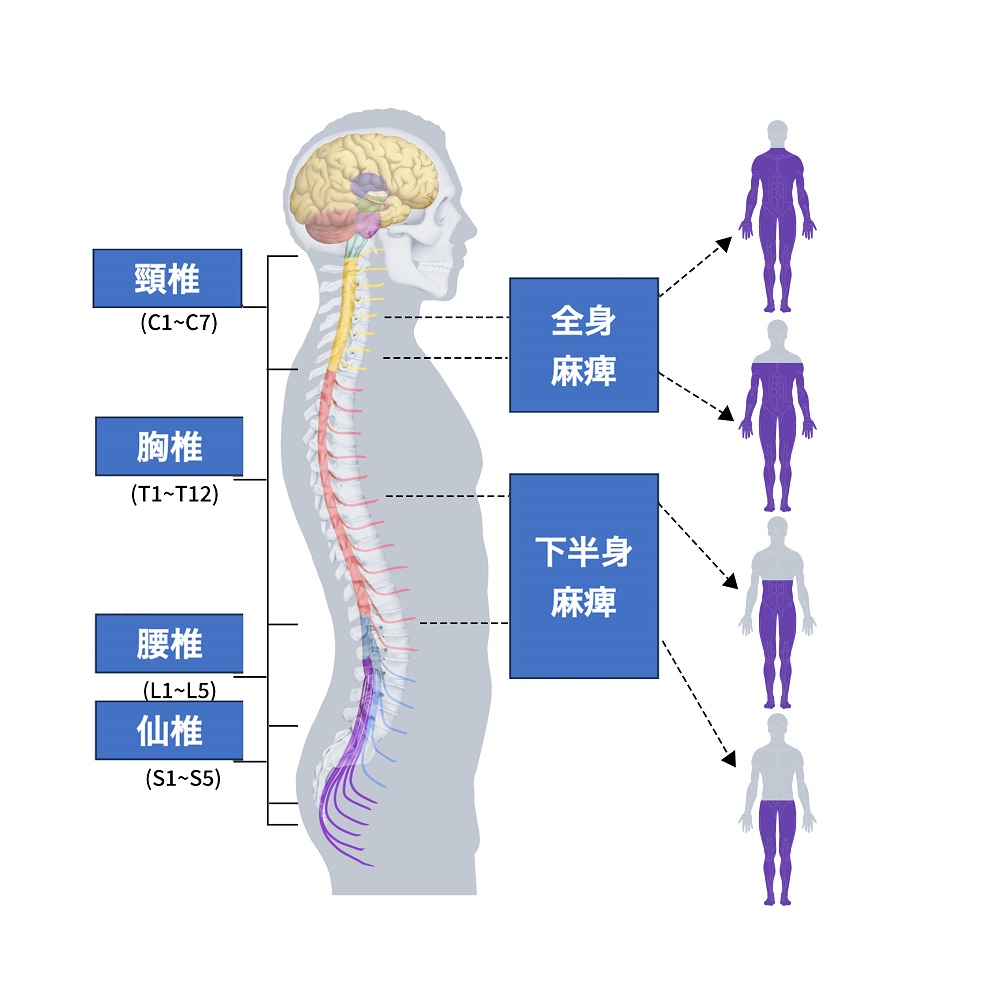

脊髄損傷のレベル

脊髄の損傷は、さまざまな体の機能を麻痺させる可能性があります。

損傷部位によって運動機能や感覚の低下·消失、内臓の機能低下·消失、痛みやしびれなども起こります。場合によっては、日常的に医療的な自己管理が必要になることもあります。

脊髄損傷はその位置と程度により、影響範囲と程度が大きく異なります。頚髄(首の部分)が損傷すると、四肢が麻痺します。特に、頚椎の少しの位置変動が麻痺の程度に大きく影響し、特に、頚髄の高位部分(通常、C5より上)で損傷がある場合、手指だけでなく、呼吸筋まで麻痺し、人工呼吸器が必要となる場合もあります。

胸·腰髄損傷の場合は、第6胸椎までの高位胸髄損傷では、腹部と背部の筋肉が働かず、体幹の安定が困難になります。その下から第2腰椎までの低位胸·腰髄損傷では症状が大きく異なります。また、これらの損傷では自律神経過反射が明らかに現れ、胸部への影響も出ることがあります。

加えて、同じ損傷位置でも、身体には個人差があるため、麻痺や障害の症状は人によって異なります。また、脊髄神経がどれだけ損傷されたかにより、全く動かない、感じない場合と部分的に動く、感じる場合に分けられます。

脊髄損傷の麻痺部位